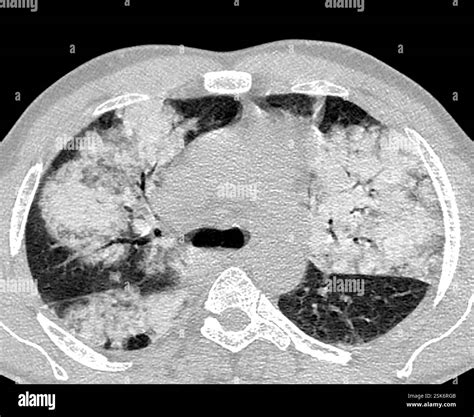

Once the scan is completed, a radiologist will interpret the images and generate a report. When viewing a Pneumonia CT Scan, medical professionals look for specific patterns of lung involvement. These patterns often indicate the type of pneumonia or the severity of the inflammatory response.

Common findings often described in reports include:

• Consolidation: This refers to the filling of air spaces (alveoli) with fluid, pus, or other material, appearing as dense, white areas on the scan.

• Ground-Glass Opacity (GGO): A hazy appearance in the lungs, indicating partial filling of air spaces or thickening of the lung interstitium. This is often seen in viral pneumonias.

• Bronchograms: The appearance of air-filled bronchi surrounded by consolidated lung tissue.

• Pleural Effusion: The buildup of fluid in the space between the lung and the chest wall.

• Nodules or Cavitation: These findings may prompt further investigation to rule out other infections or malignancy.

It is important to remember that these findings must always be correlated with the patient's symptoms, laboratory results, and clinical history. A report with "positive findings" does not always imply a worst-case scenario, as many patterns are typical of common bacterial or viral infections.